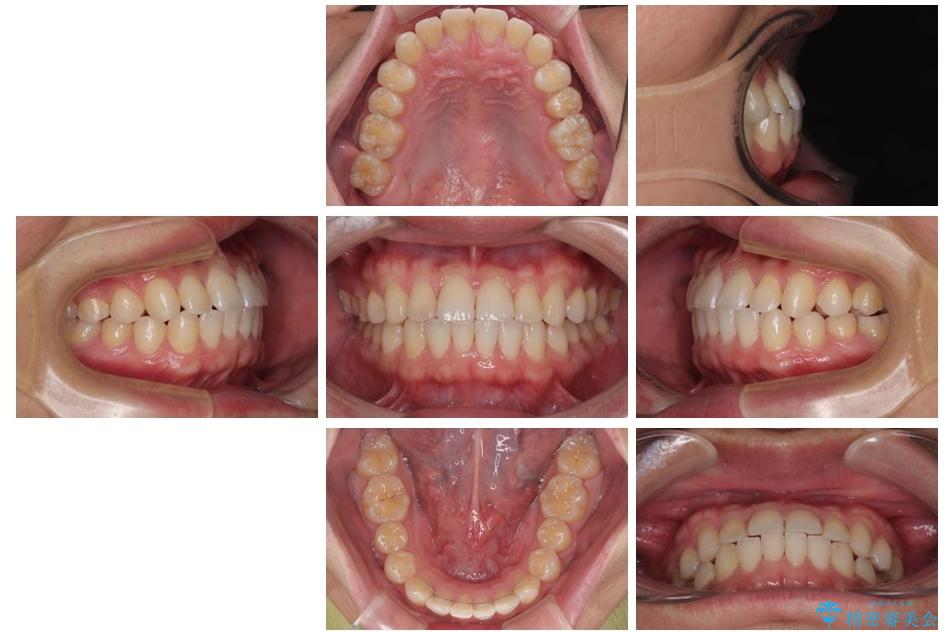

治療前

• 前歯のガタガタ・奥歯のかみ合わせ(シザーズバイト)を改善|1年半で完了したメタルブラケット矯正 治療前画像

治療後

• 前歯のガタガタ・奥歯のかみ合わせ(シザーズバイト)を改善|1年半で完了したメタルブラケット矯正 治療後画像